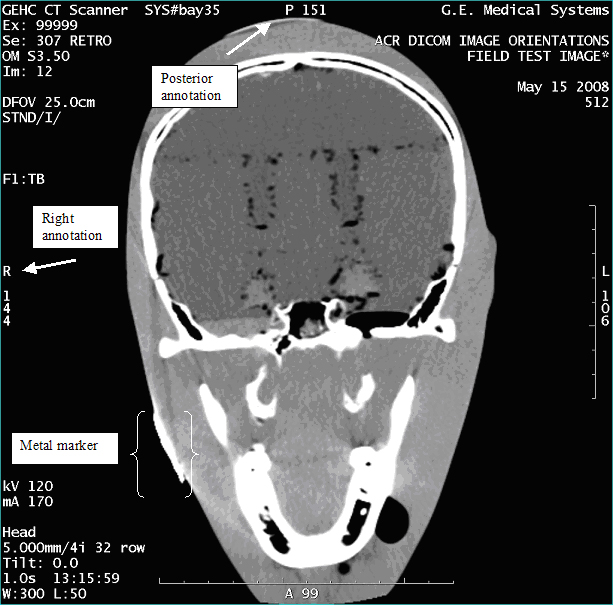

- With the support of the site personnel, examine the images sent

to the Review Station (i.e., 12 series, each with 1 image) and compare

their orientation to the images in this document.

- Each image contains a metal marker on the phantom's right cheek.

- Each image in this document contains a description of the expected

orientation of the metal marker (i.e. to prove Left and Right) as

well as the Posterior and Anterior orientation description.note:

The sample images included in this document use “R”, “L”, “P”, and “A” for “Right”, “Left”, “Posterior” and “Anterior” orientation. The Hospital Review Station may use a different style of annotation. The style used is not relevant to this procedure.

- Each image in this document has sufficient space to store the observed results for up to 4 Review Stations.

- Enter ‘Y’ in the space to indicate the observed result matches the expected.

- Enter ‘N’ in the space to indicate the observed result does not match the expected.

- Enter “NA” in the space if a column is not being used.

- Repeat for each destination.

Figure 3. Exam 99999, Series 307